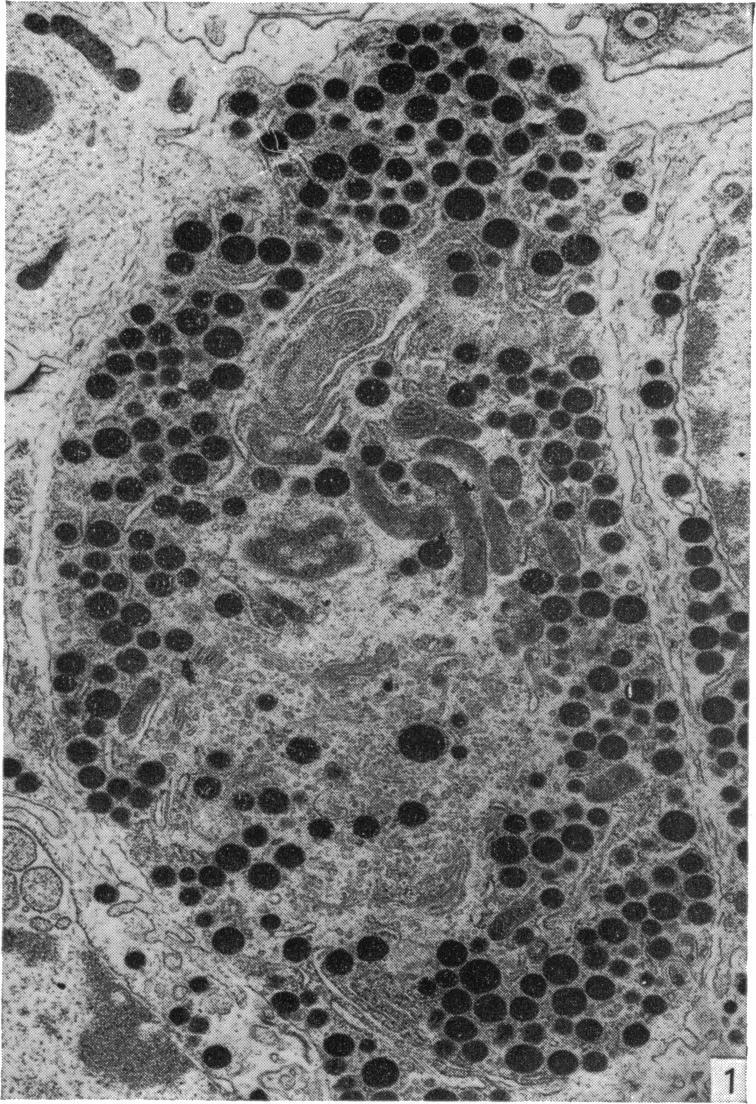

A technique is described which permits the maintenance for up to 8 days in organ culture of explanted rat pituitary glands. Electron microscope studies showed that the cultured glands (whether treated with gonadotrophin-releasing hormone (GnRH) or not) were almost identical to controls in appearance, although the stellate (follicular) cells seemingly were eliminated in vitro. Gonadotrophs and prolactin-secreting cells in male and female pituitary glands were similar in appearance both in vivo and in vitro to comparable cells described by other authors. There was some evidence for an increase in the secretory activity of these cell types (particularly gonadotrophs) when the explants were treated with GnRH. The present technique thus provides a suitable and valid 'model' with which to study the effects of GnRH and steroid hormones on the release and synthesis of FSH and LH in vitro.

本文描述了一种技术,该技术可使离体大鼠垂体腺在器官培养中维持长达8天。电子显微镜研究表明,培养的腺体(无论是否用促性腺激素释放激素(GnRH)处理)外观上与对照几乎相同,尽管星状(滤泡)细胞似乎在体外被清除。雄性和雌性垂体腺中的促性腺激素细胞和催乳素分泌细胞在体内和体外的外观与其他作者描述的同类细胞相似。有证据表明,当外植体用GnRH处理时,这些细胞类型(特别是促性腺激素细胞)的分泌活性会增加。因此,本技术提供了一个合适且有效的“模型”,用于研究GnRH和类固醇激素对体外FSH和LH释放与合成的影响。